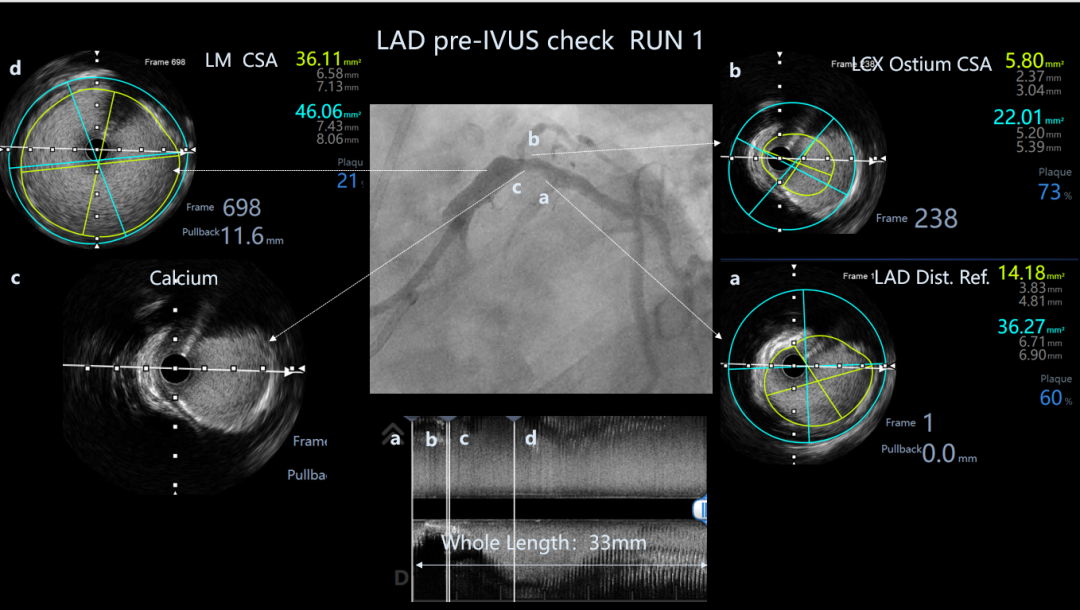

LAD pre-IVUS check RUN 1 looking for entry point

LAD pre-IVUS check RUN 2

LAD post-IVUS check RUN 3

CTA示LAD近中段严重钙化、LAD开口无残端、RCA极度迂曲。

首选IVUS找开口、因LM直径达6.5mm,无法看清分支方向。